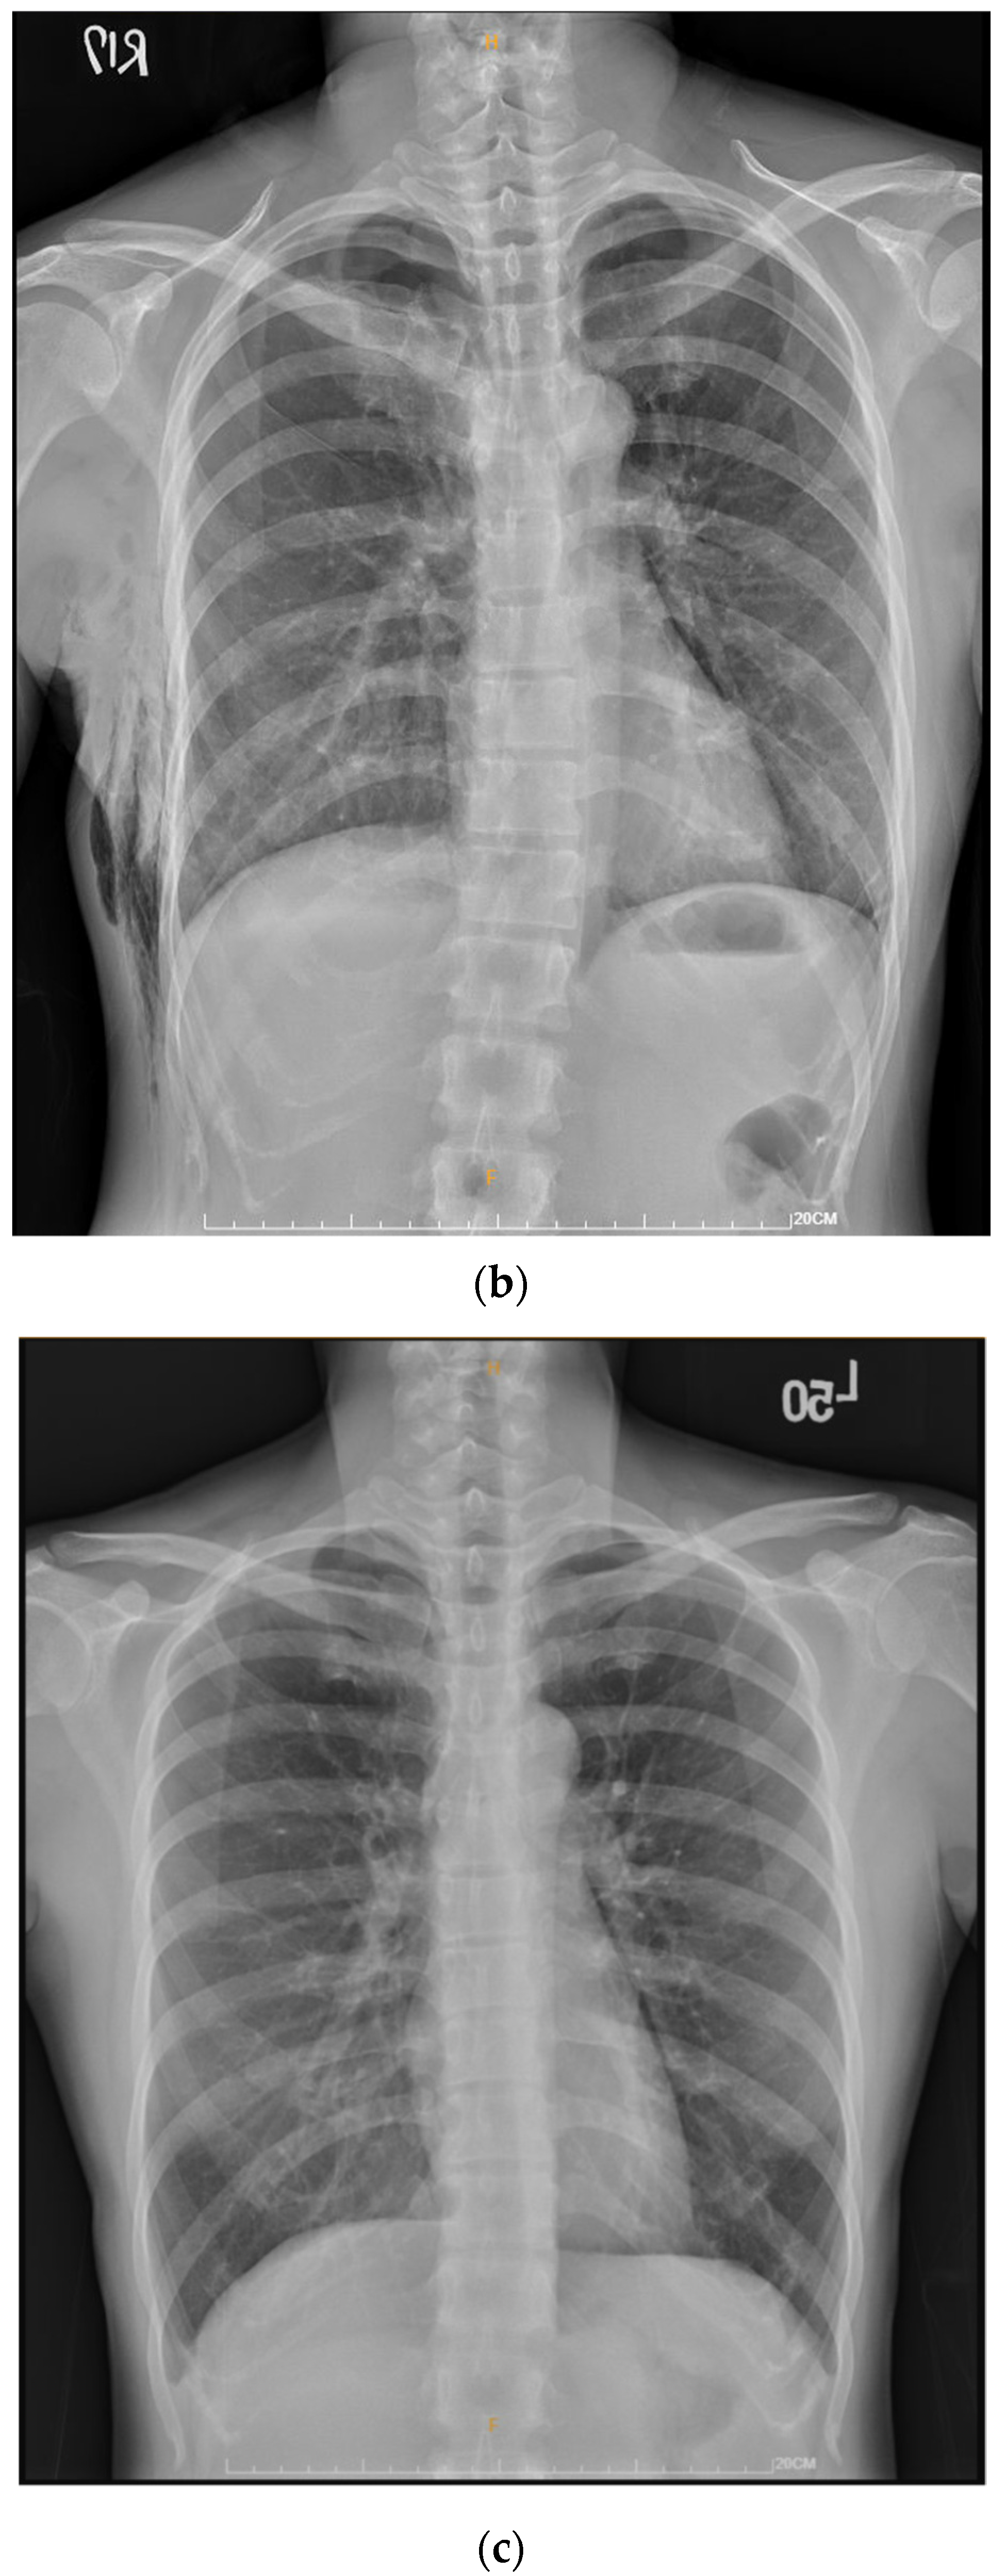

2.2. Technique for Drainless Uniportal VATS Wedge Resection